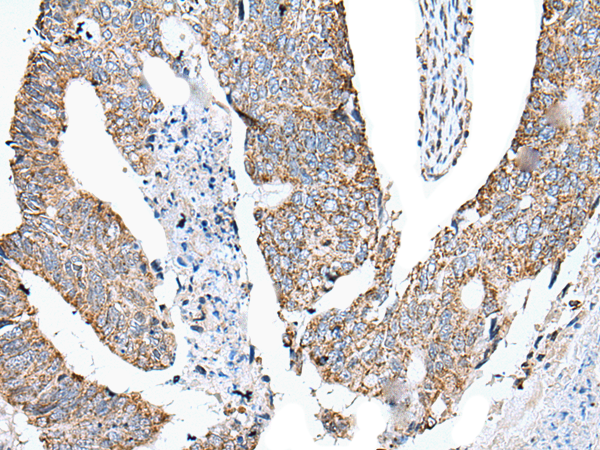

IHC positive control: |

Human colorectal cancer and human esophagus cancer |

IHC Recommend dilution: |

25-100 |